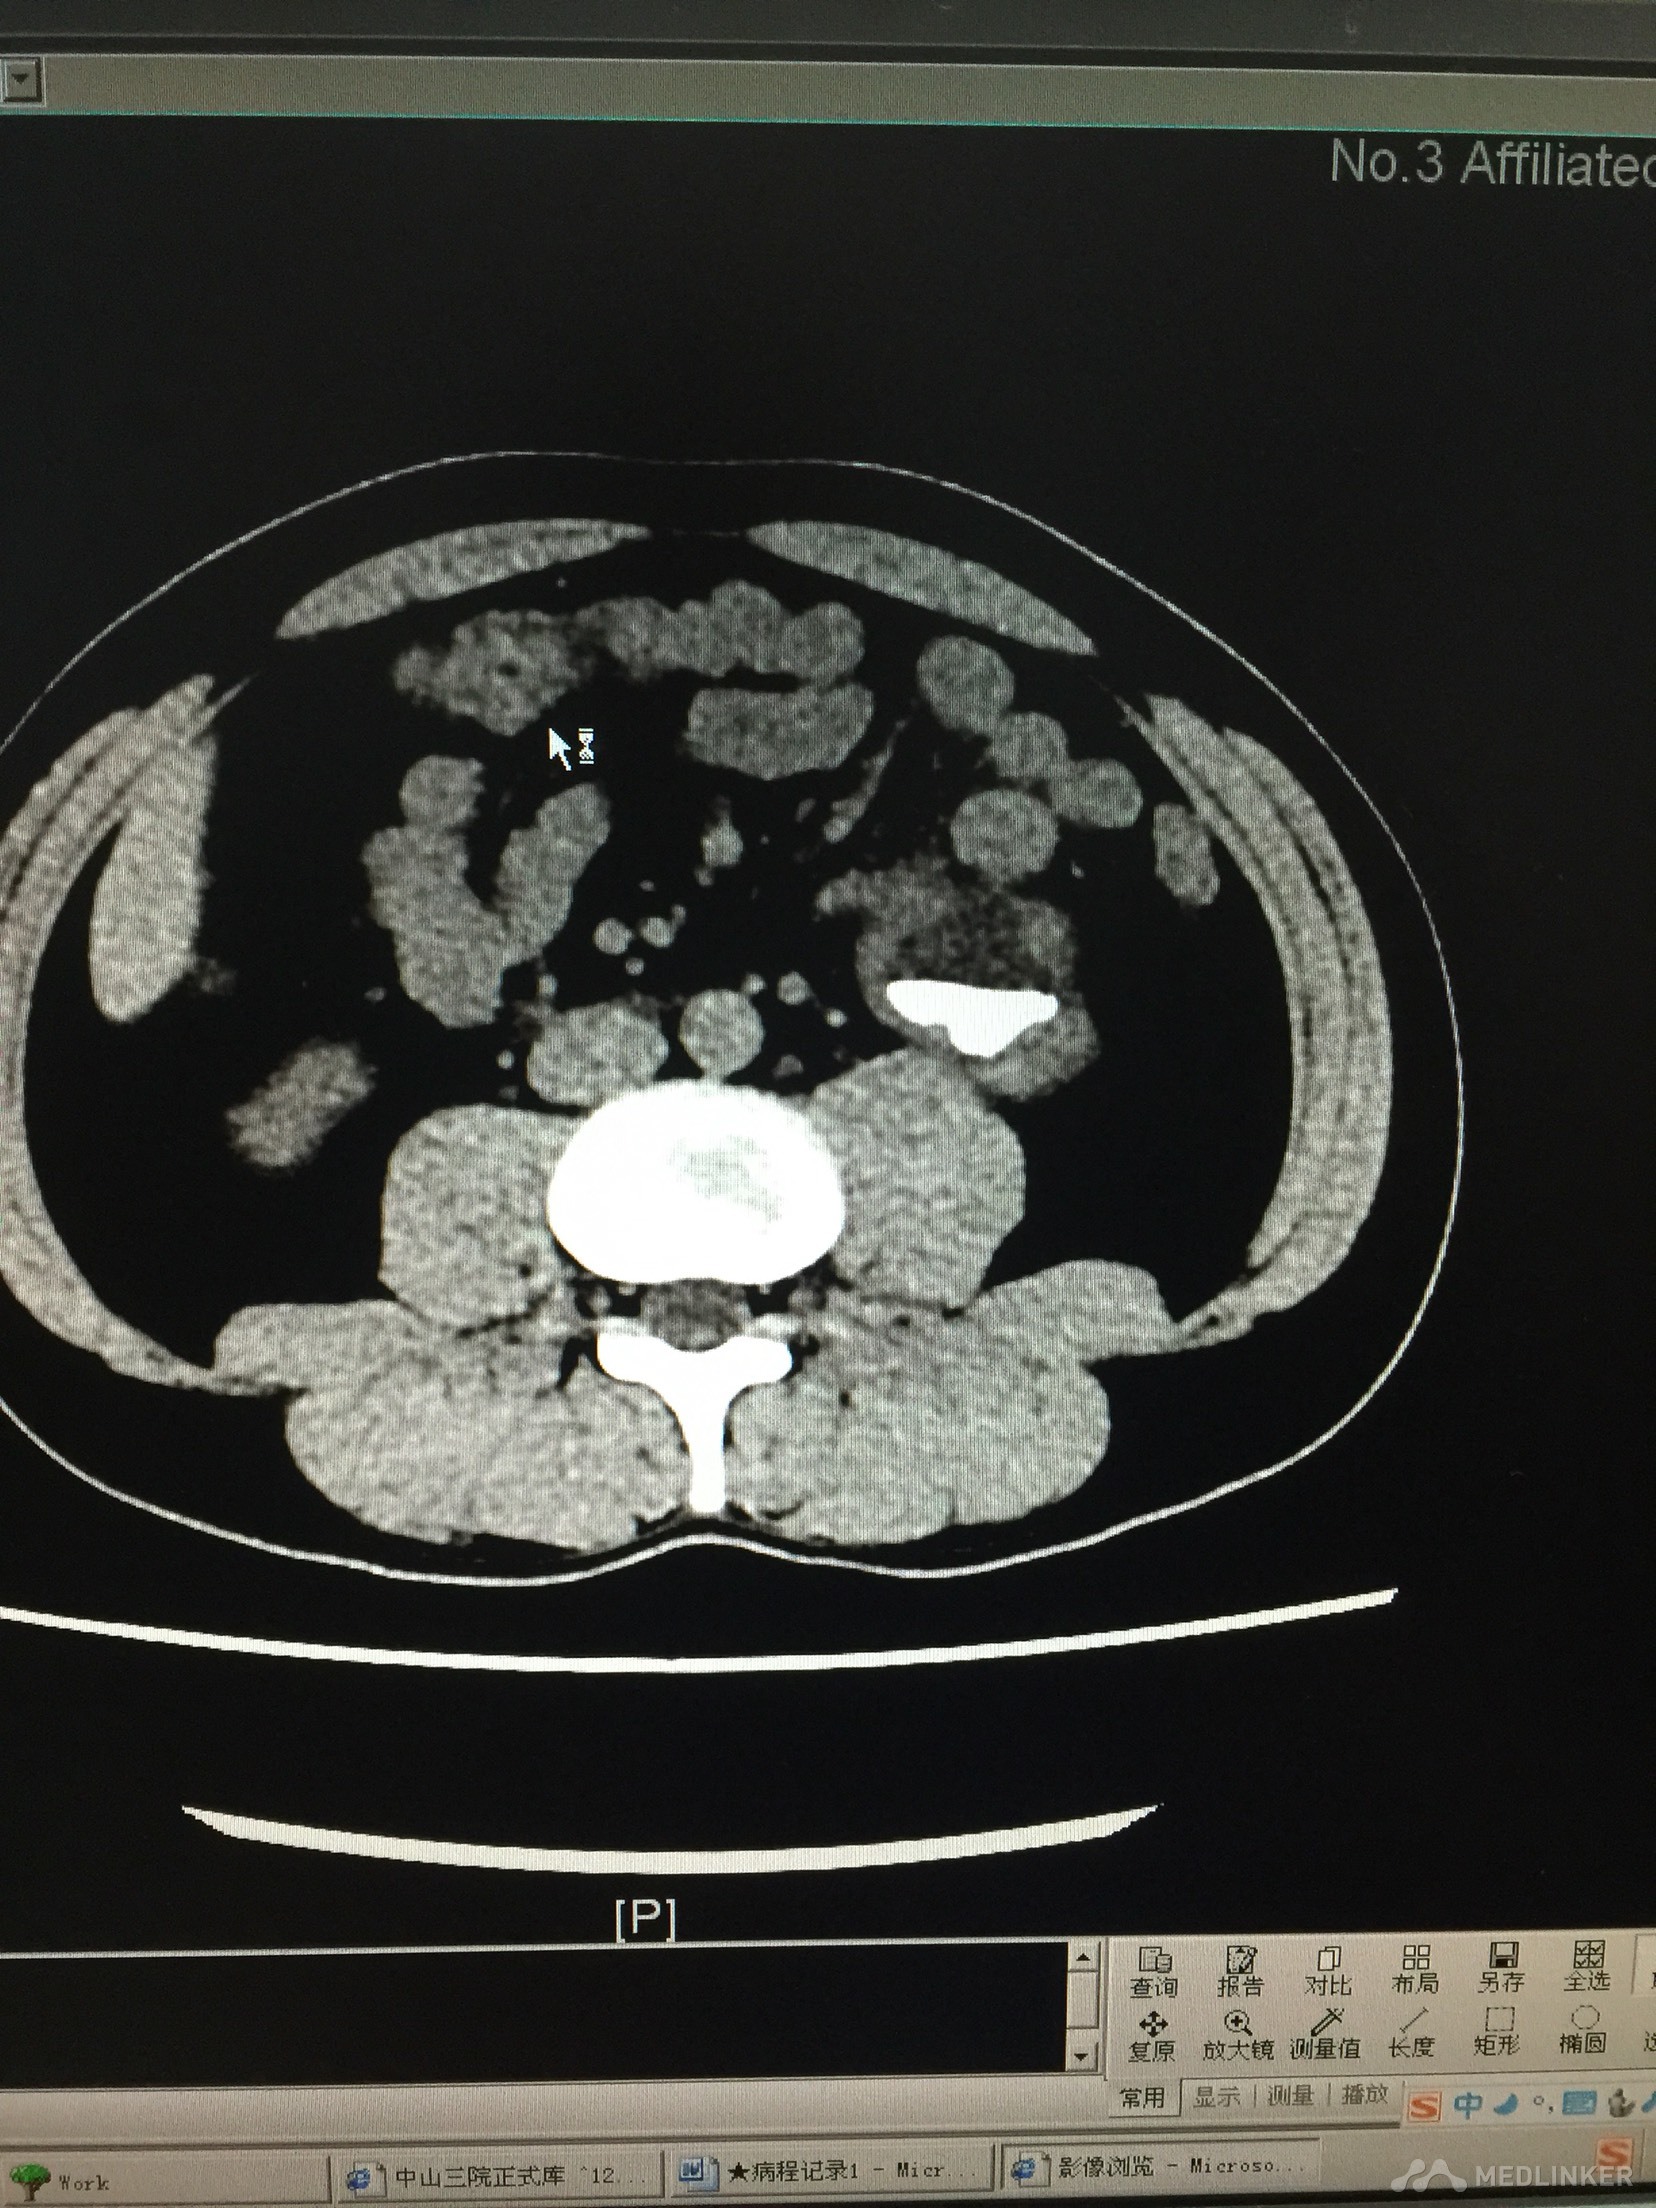

肾结石合并肾积水?

患者体检发现肾结石,但此时已经严重肾脏积水,患者诉并没有任何不适。为什么肾脏损害如此严重,症状却没有呢?